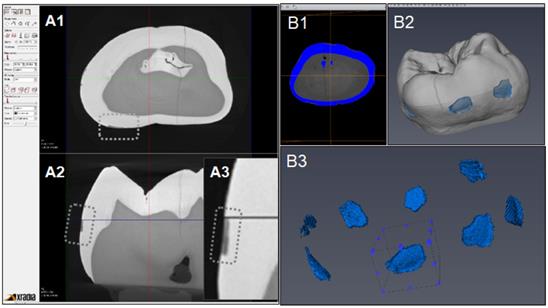

Figure 6 indicates the experimental protocol. Fifty-six artificial lesions were created on intact flat surfaces (interproximal, buccal and lingual) using 12 extracted human teeth (Figure 1). Two coats of enamel varnish were applied to the flat surface of each tooth, leaving 4 ~ 6 exposed windows of approximately 2.0 mm diameter. Each tooth was then submerged in a 50ml centrifuge tube containing 5 ml of 0.5 M lactic acid demineralization solution for 3 days and the solution was replaced every 24 hours. Each tooth was rinsed with doubled distilled water (ddH2O: DD) twice for 60 seconds each time. The lesion depth was measured using a high-resolution 3D X-ray microscope (Xradia MicroXCT-200, Zeiss, Figure 7 -A1, -A2, and -A3). All teeth were scanned using the same filter, magnification, exposure time, kV and voltage. Following reconstruction, lesion depths were calculated using Avizo 8.1 (Figure 7 -B1, -B2 and -B3). A total of 33 lesions with initial depths of 150 µm (±21.3) and initial volume of 235 E+07 µm3 (46.5) were used for the experiment.

Figure 7

CT images acquisition and measurement of lesion volume using Aviso. A1: Xradia images reconstructed. A2: Shallow lesion were observed in the axial surfaces. A3: Enlarged image of lesion. B1: Original image for Aviso. B2: The 3D presentation of lesions. B3: The volume on each lesion were calculated.